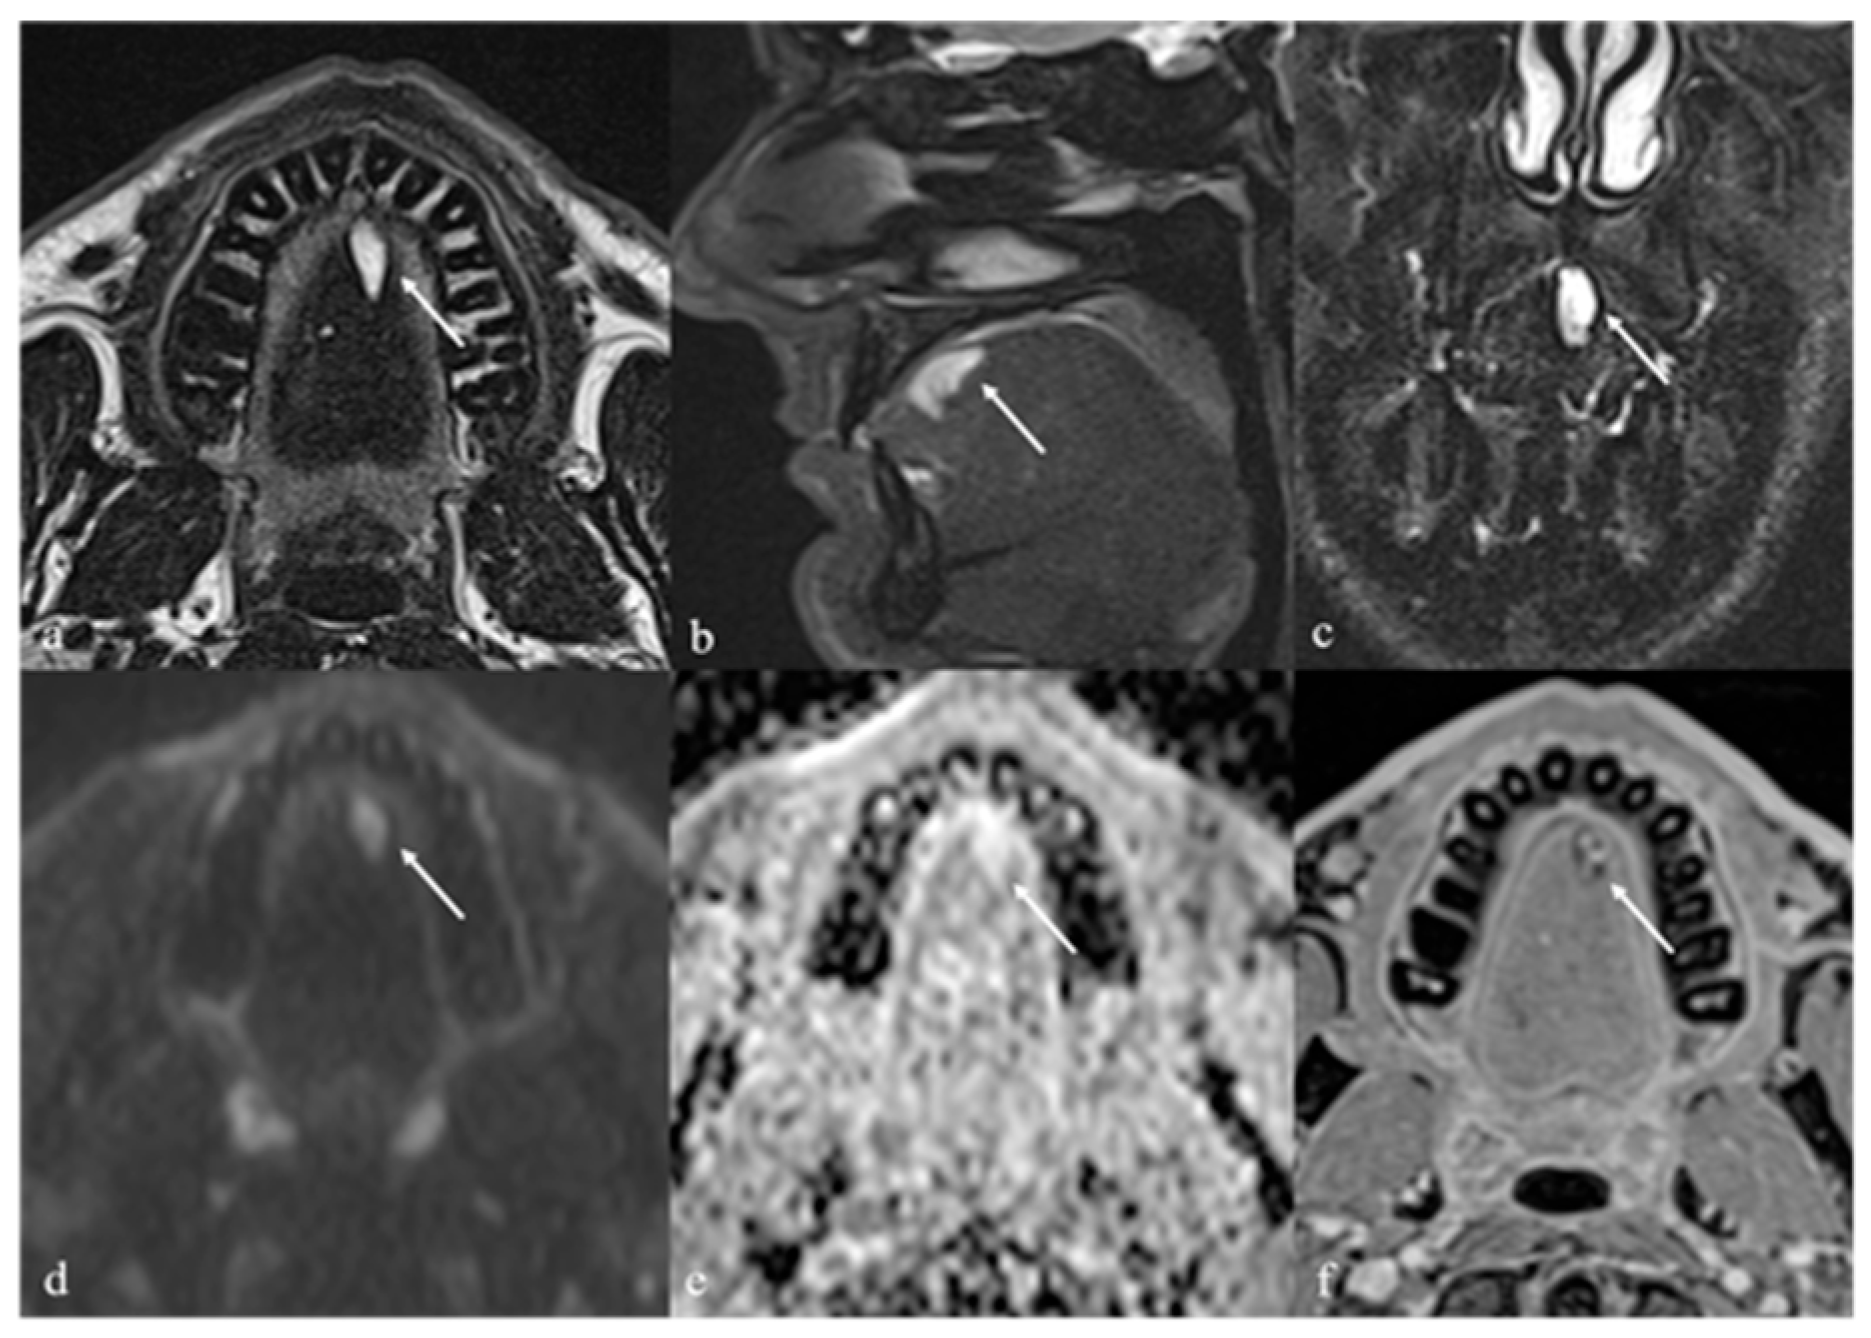

8. Lingual Abscess

| Abscess [17] | CT, MRI: peripheral enhancement MRI: core of the lesion shows high SI on DWI, and restricted diffusion with low values on ADC map | Submucosal malignancy |